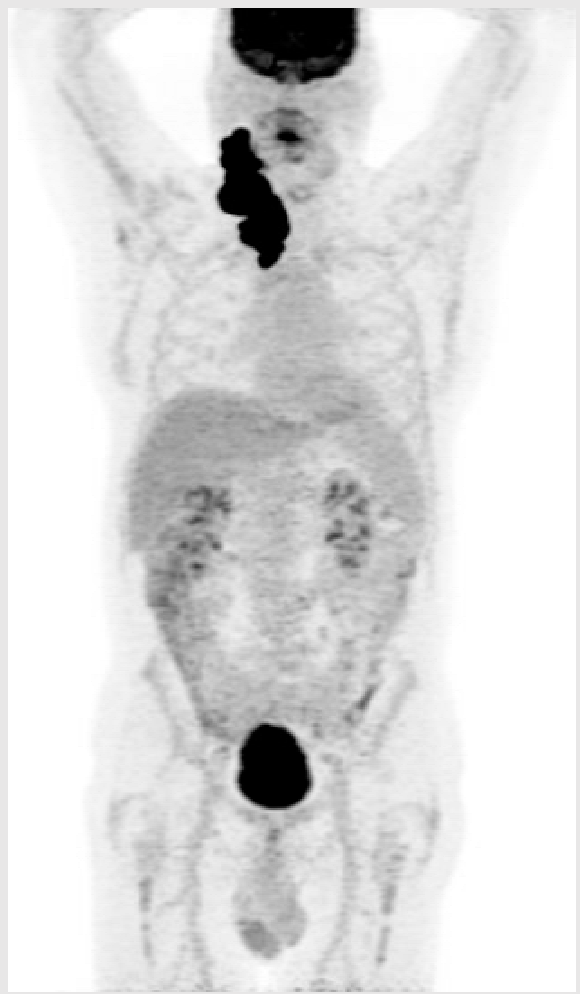

3.3. Illustrative Case 3

Key Clinical Features

| ![]() ![]() |

Key Points for Illustrative Case 3